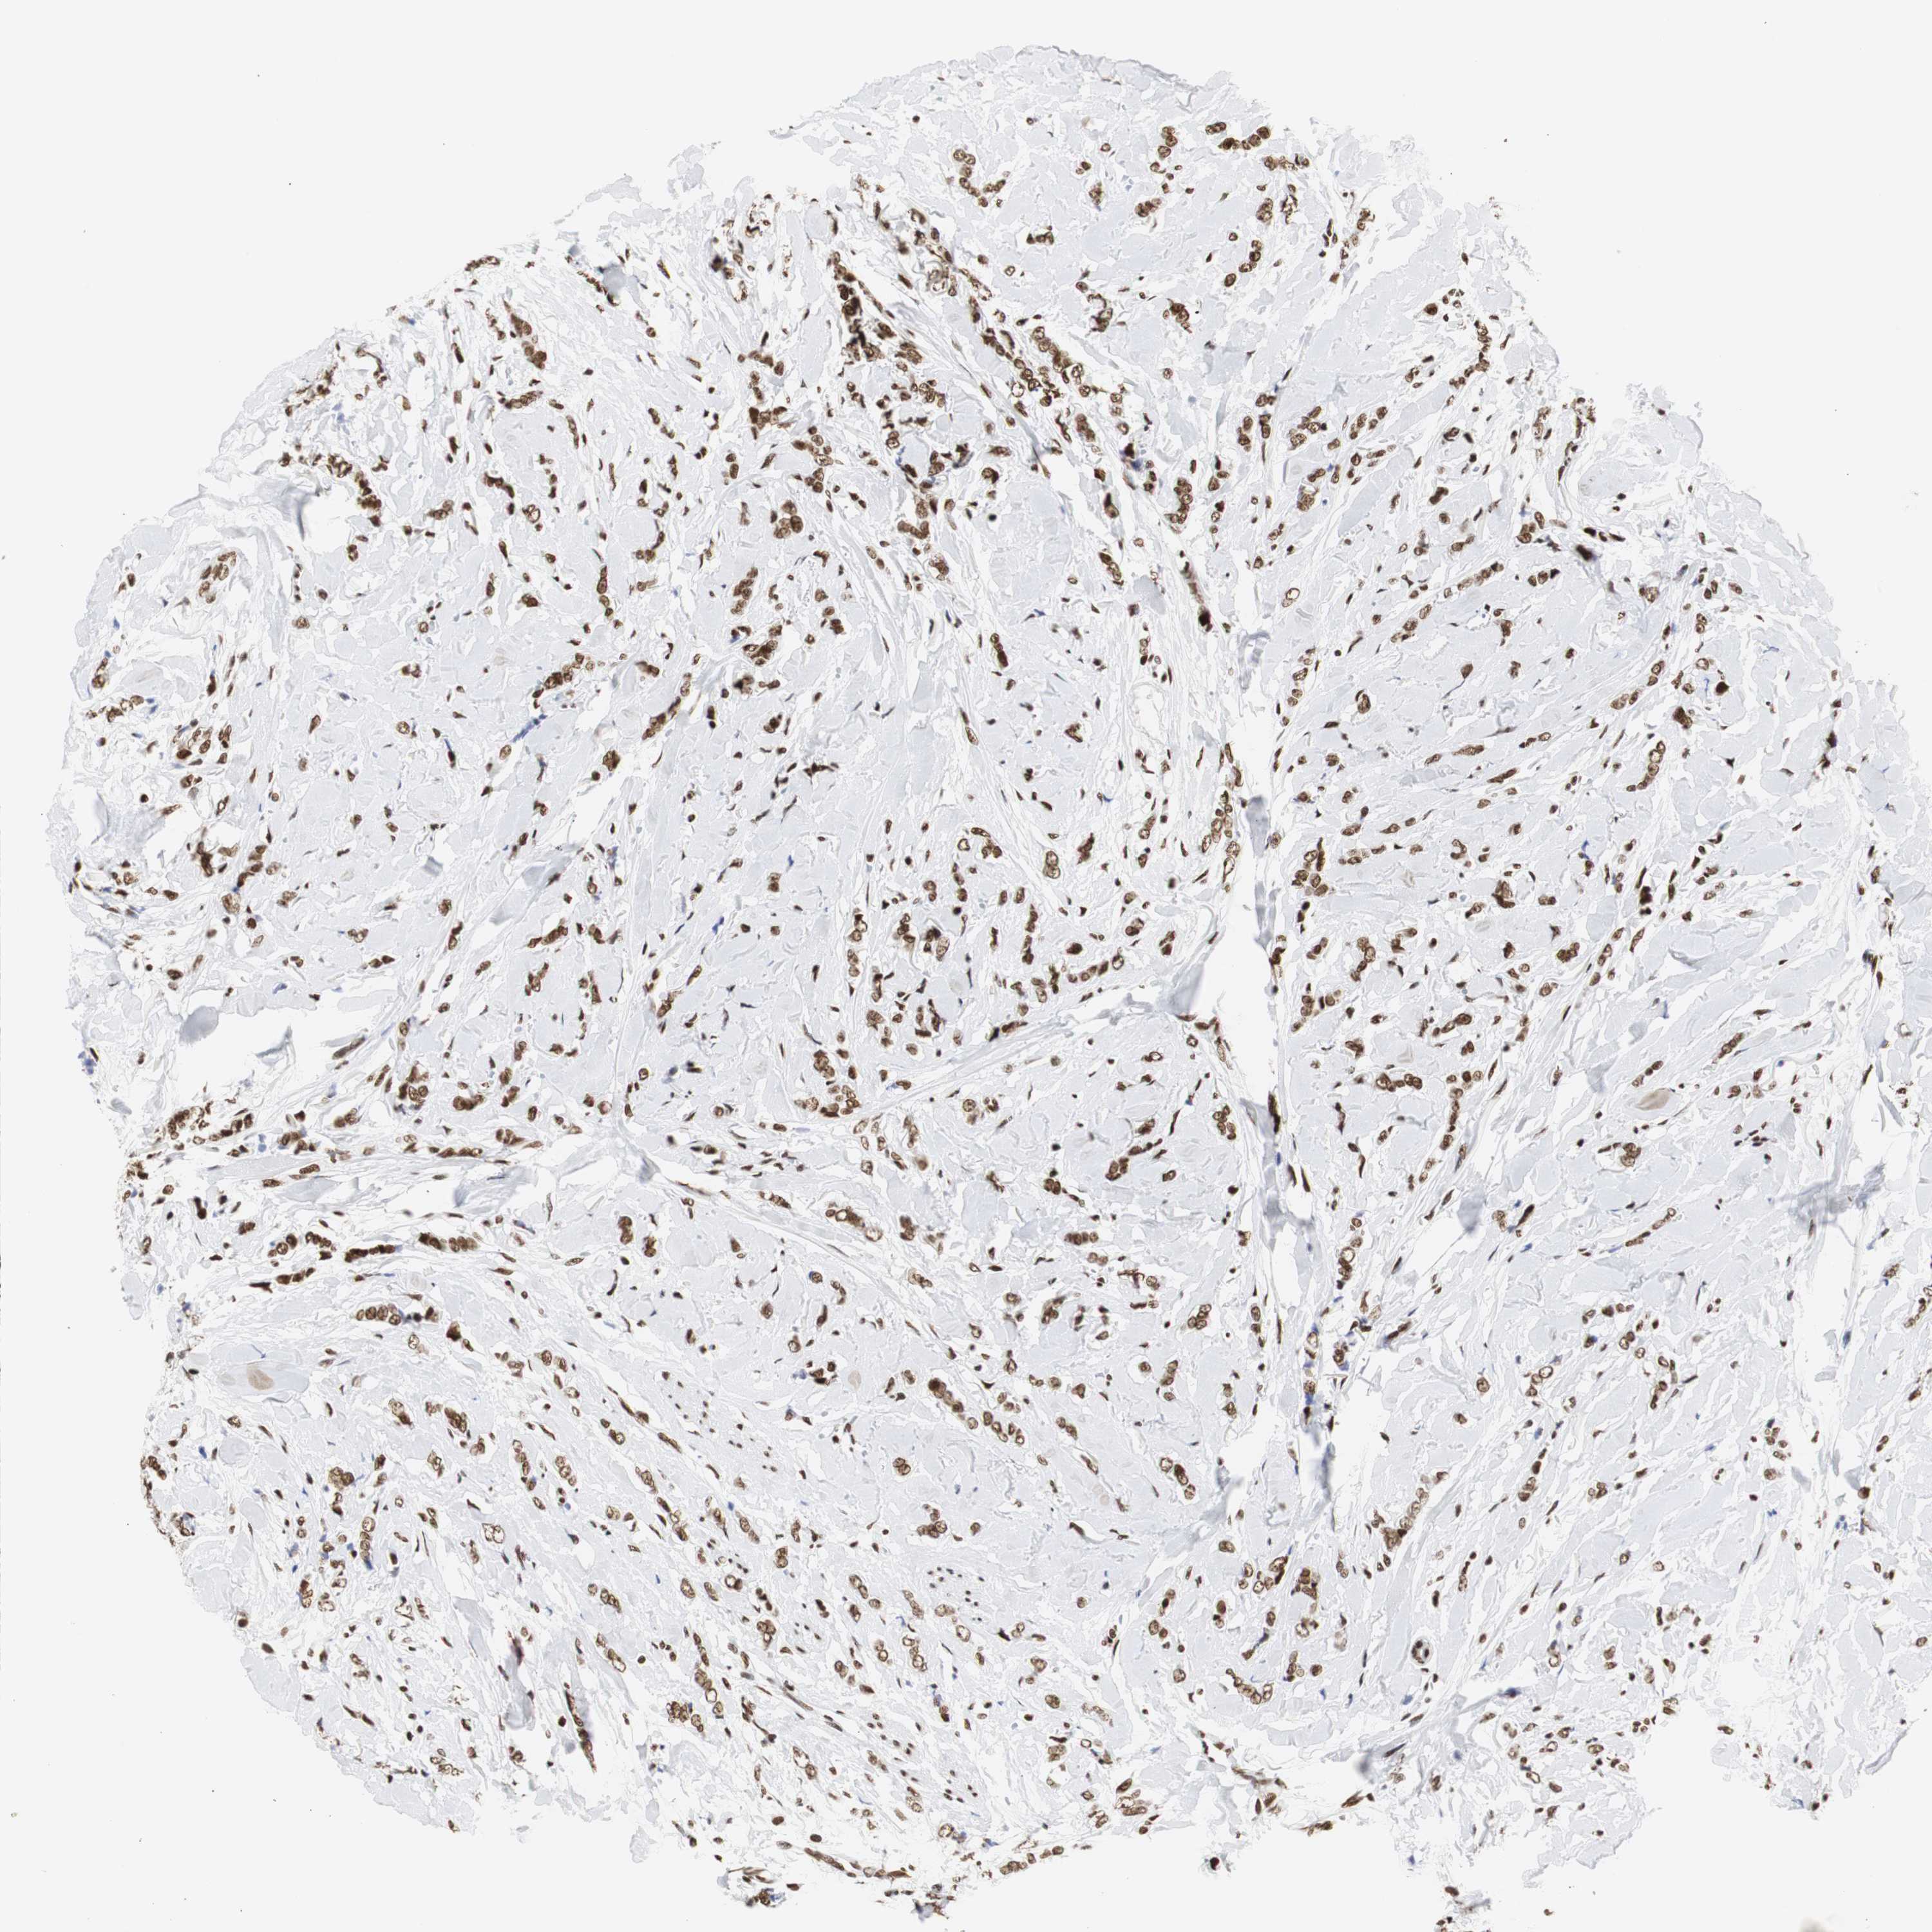

CANCER BREAST CANCER Show tissue menu

BRCA TCGA BRCA VALIDATION PROTEIN EXPRESSION